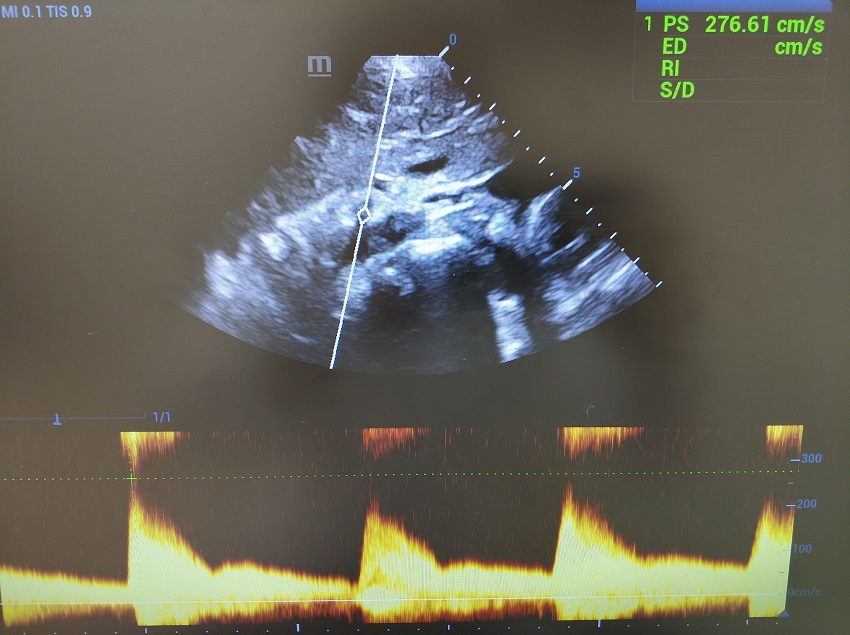

Повторяем маневр, контрольный объем скользит в чревный ствол. Прибор переходит на визг,  ручка Scale вправо - увеличиваем шкалу и пульсация затихает. Калипер поднимается на вершину систолического пика, PSV  276  см/сек. Максимум ли? Переходим в режим постоянно волнового CW-допплера, фокус в зону истока чревного ствола. Да, максимум.